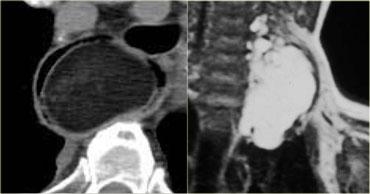

Hãy mô tả hình ảnh bên trái.

Sau đó tiếp tục.

CT cho thấy một khối trung thất trước có tỷ trọng tương đương nước.

Đây là hình ảnh điển hình của nang tuyến ức.

CT cho thấy một khối nằm ở trung thất trước.

Khối có dạng nang nhưng có các vách ngăm thuốc cản quang dạng đặc.

Đây là dấu hiệu rất đặc trưng của u tế bào mầm.

Nhiều người cho rằng u tế bào mầm phải chứa mỡ và nếu tổn thương không chứa mỡ thì không thể là u tế bào mầm.

Cần nhớ rằng chỉ khoảng 60% u tế bào mầm có chứa mỡ, do đó sự vắng mặt của mỡ không loại trừ u tế bào mầm khỏi chẩn đoán phân biệt.

Thành phần đặc càng nhiều thì khả năng u tế bào mầm ác tính càng cao.